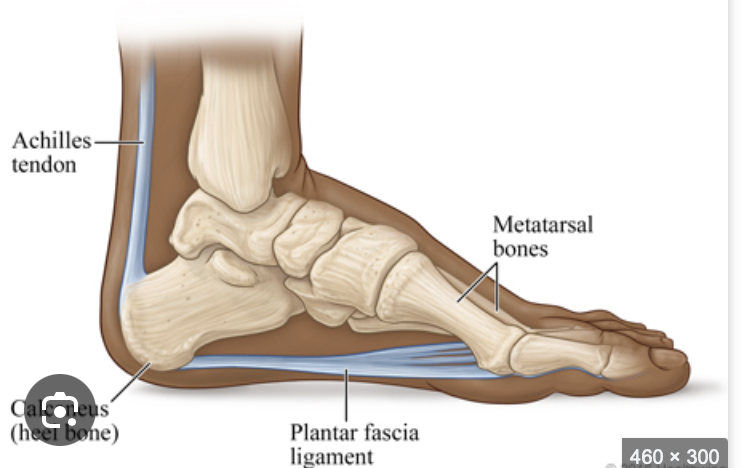

What is the role of the plantar fascia? [1]

Plantar fascia (or aponeurosis) is a band of fibrous tissue that acts as a shock absorber providing stability within the foot and cushioning for force transmitted through the lower limbs.

Attache the calcaneus, travels along the sole of the foot and connects to the flexor tendons of the toes

What causes plantar fasciitis? [1]

Age: causes degenerative changes in the plantar fascia

Obesity

Foot biomechanics: high foot arch or flat feet can add additional strain

Tight achilles tendon

Prolonged standing or walking

Sudden increase in physical activity

Trauma

Describe the clinical presentation of plantar fasciitis [3]

Inferior heel pain on pressure (100%).

- Usually worse on the first steps out of bed in the morning or after period of inactivity

- pain on medial aspect of heel

- May ease on walking but worse with heavy activity or standing

- Tenderness to palpate

- Pain that worsens after exercise, not during